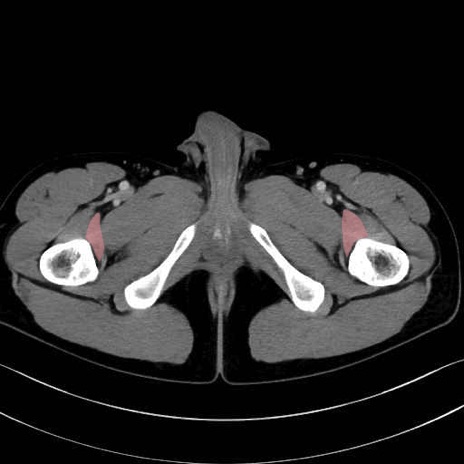

内閉鎖筋 (Obturator internus)

外閉鎖筋 (Obturator externus)

大腿方形筋 (Quadratus femoris)